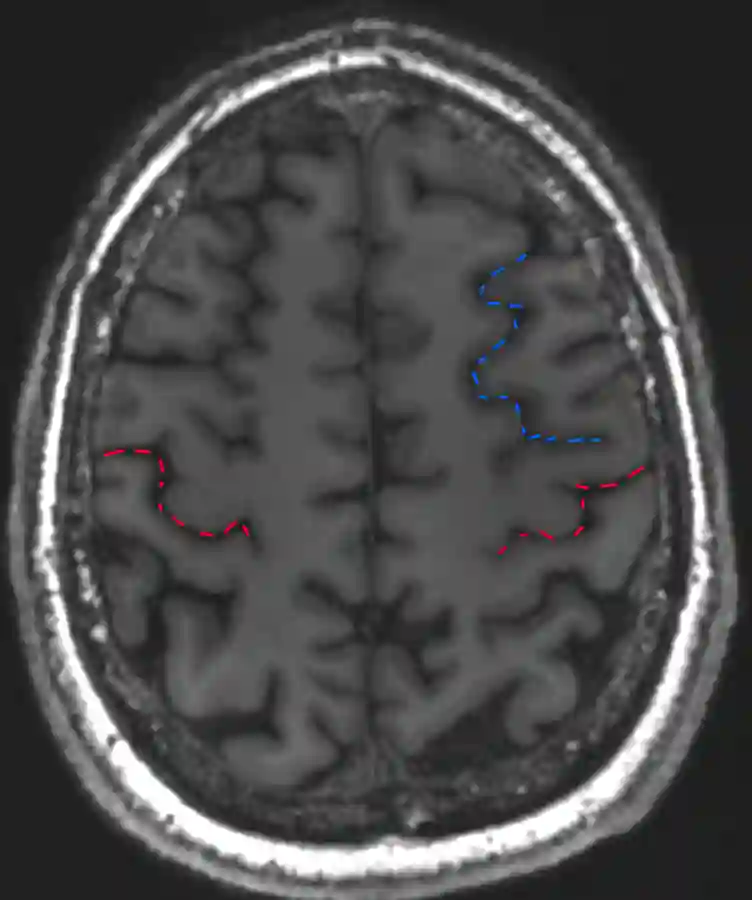

Bracket Zeichen zur Identifikation des Sulcus centralis

Axiales T1 MRT mit eingezeichnetem Bracket Sign in blau, welches den Sulcus marginalis darstellt. Das Bracket Sign stellt die Ausläufer des Sulcus cinguli dar, welcher als Ramus bzw. Sulcus marginalis bezeichnet wird. Direkt anterior des Bracket Zeichens befindet sich der Sulcus centralis (rot markiert).

L-Sign Sulcus centralis

Darstellung des L Zeichen (blau markiert) im axialen MRI